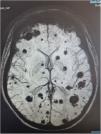

Más datosMujer de 23 años que sufre cuadro de fallo hepático agudo grave con estudio etiológico no concluyente, y que recibe tratamiento corticoideo durante un mes por sospecha autoinmune. Sufre deterioro neurológico y se realiza escáner de cráneo con múltiples lesiones ocupantes de espacio que motivan la realización de un escáner total body donde se objetivan microabscesos en órganos abdominales y resonancia de cráneo con incontables áreas focales de alteración de la señal supra e infratentoriales con componente hemorrágico central y áreas de restricción de la difusión en la periferia que tras administración de contraste muestran realce periférico fino, todo ello compatible con encefalitis séptico-embólica. Los hemocultivos y la ecografía transesofágica descartaron la sospecha de endocarditis. No fue posible la punción lumbar por trombocitopenia. Finalmente se realiza determinación de A. fumigatus por PCR en lavado broncoalveolar que fue positiva. Recibe tratamiento antifúngico con mala evolución y finalmente desarrolla muerte encefálica (fig. 1).